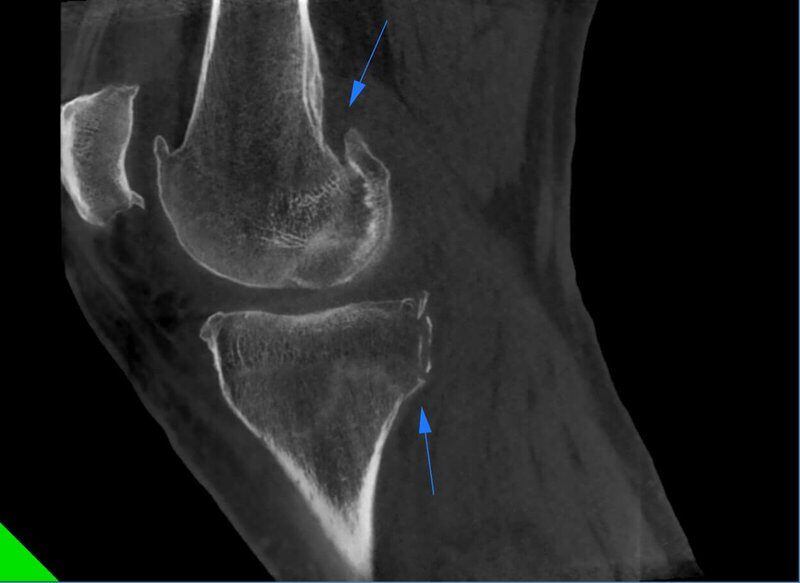

Frattura multipla ginocchio